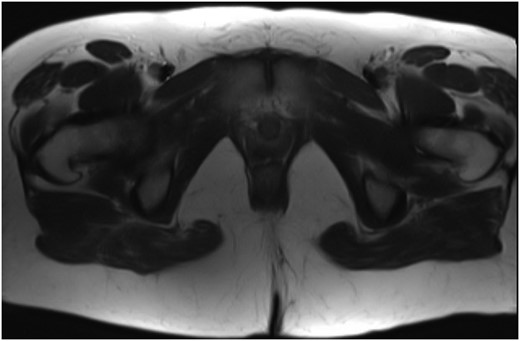

Final pathology revealed a moderately cellular neoplasm with cellular processes extending around blood vessels, formation of perivascular pseudorosettes, and areas of myxoid degeneration (Fig. 1). The neoplastic cells were strongly positive for glial fibrillary acidic protein (GFAP), CD-99, and CD-56, all of which supported the morphologic diagnosis of ependymoma (Fig. 2). The cephalad margin was positive for tumor. A follow up magnetic resonance (MR) of the pelvis and neuraxis was obtained, which demonstrated post-surgical changes and no evidence of persistent tumor (Fig. 3). After evaluation by neurosurgery, full neuro-axial imaging was performed and did not show any evidence of tumor or additional pathology. Excision of the positive cephalad margin and adjuvant chemotherapy or radiotherapy was not recommended. Long-term surveillance with frequent clinical examinations and pelvic MR was established.

MR of the pelvis showing no evidence of persistent or recurrent sacrococcygeal ependymoma.